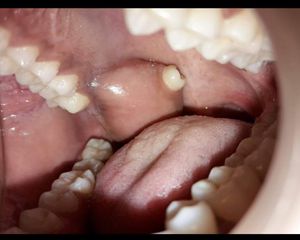

Ectopic tooth

Dentistry

Tooth

Ectopic